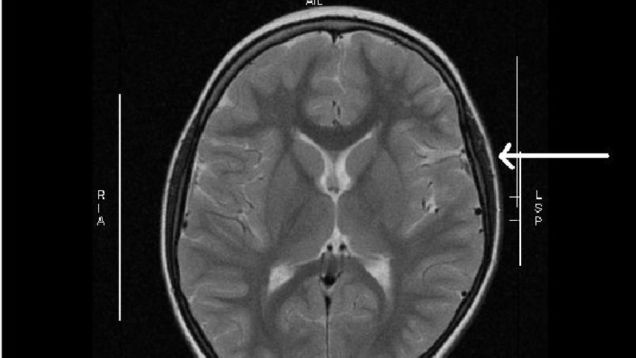

Health care costs in the U.S. are rising most everywhere, and a new study out Wednesday suggests that people seeking care for neurological problems are no exception. The study found that people with private insurance are increasingly paying out-of-pocket for services like MRIs, and that these costs have risen over theā¦

Source: Gizmodo – Patients Are Paying More Out of Pocket for MRIs and Other Brain Health Exams